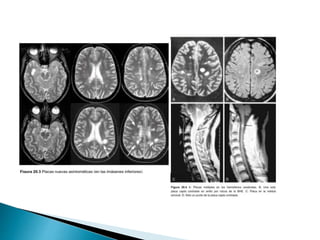

 Características de las lesiones

desmielinizantes en 95% de los casos:

◦ Hipointensas T1.

◦ Hiperintensas T2.

◦ Ovoides / forma de anillo abierto.

◦ Diámetro de 3 a 6 mm.

◦ Bordes brumosos mal definidos.

◦ Reforzamiento en T1 GDTPA.

 Características delas lesiones desmielinizantes en 95% de los casos: ◦ Hipointensas T1. ◦ Hiperintensas T2. ◦ Ovoides / forma de anillo abierto. ◦ Diámetro de 3 a 6 mm. ◦ Bordes brumosos mal definidos. ◦ Reforzamiento en T1 GDTPA. Enfermedades desmielinizantes del sistema nervioso central O. Fernández, V. E. Fernández y M. Guerrero - Medicine. 2015;11(77):4601-9